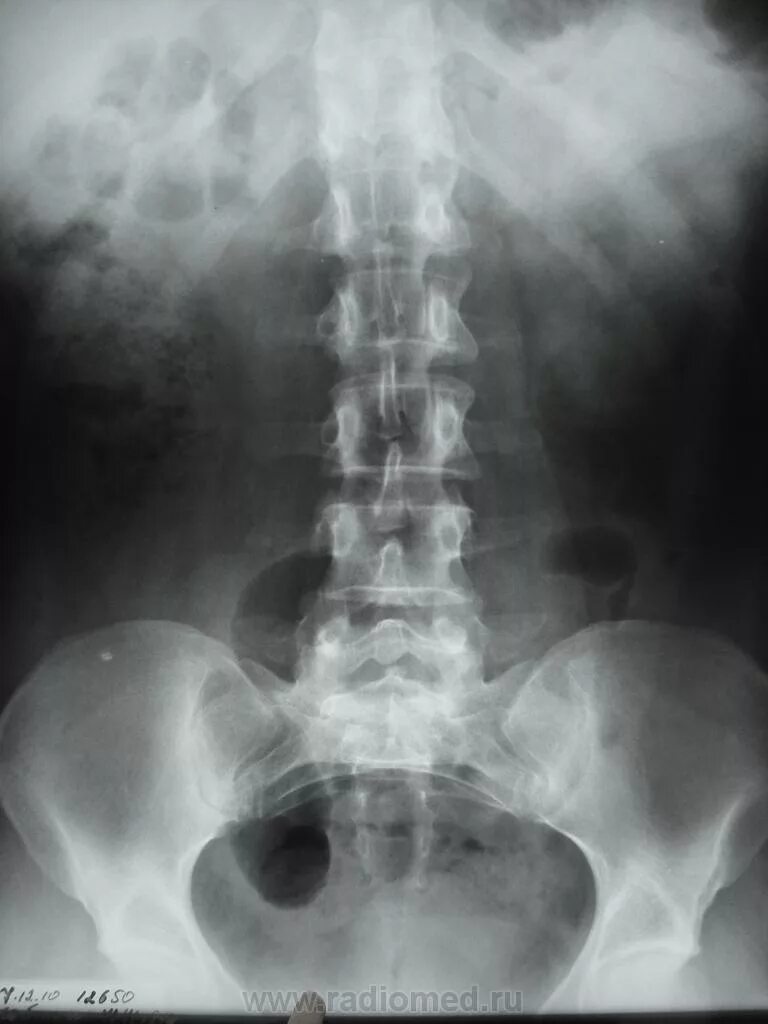

Урография с контрастом